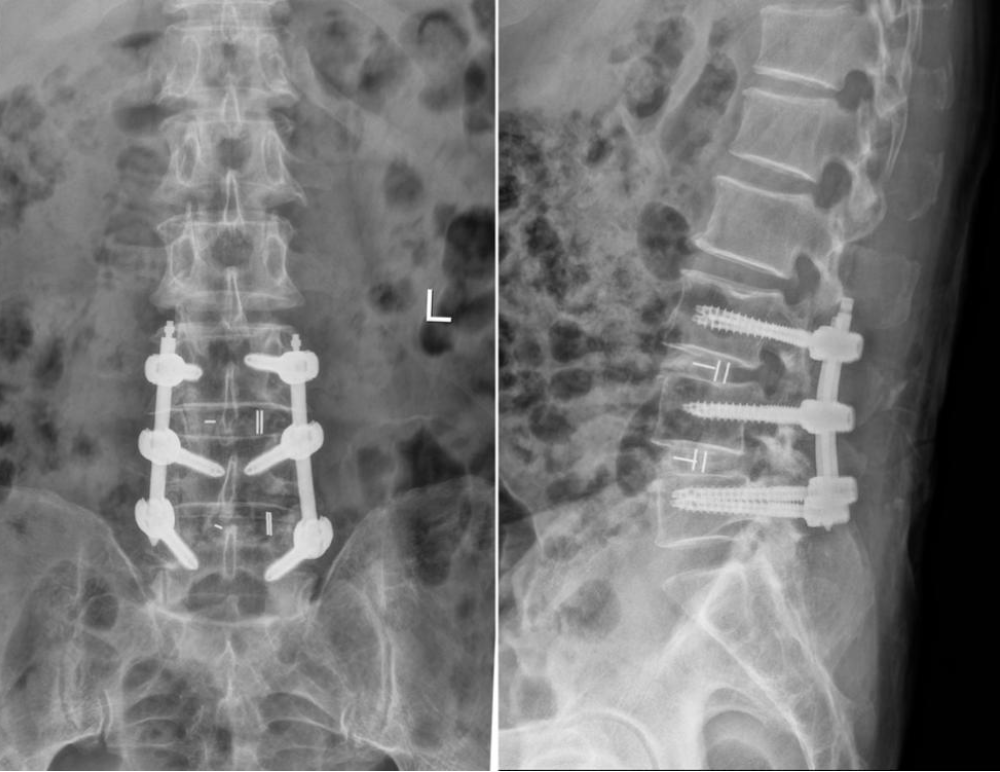

手术过程中,团队凭借丰富经验与默契配合,在UBE内镜清晰视野下,依次对L3-L4、L4-L5节段进行双侧神经减压、间盘切除,并置入椎间融合器与内固定装置,复位滑脱椎体。整个手术操作精细,出血少、损伤小,成功解决了患者双节段的腰椎病变。

术后X线:腰椎滑脱复位,融合器横置恢复腰椎曲度